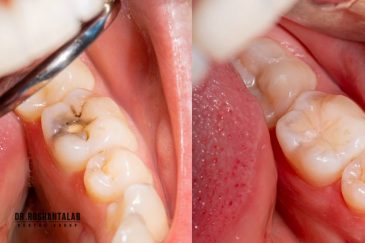

از عصب کشی و درمان ریشه دندان گرفته تا جراحی لثه و کشیدن دندان، تمامی مراحل توسط متخصص ترمیم دندان مدیریت میشود. ارائه باکیفیتترین خدمات ترمیم دندان برای سلامتی شماست.کاشت ایمپلنت فوری دندان